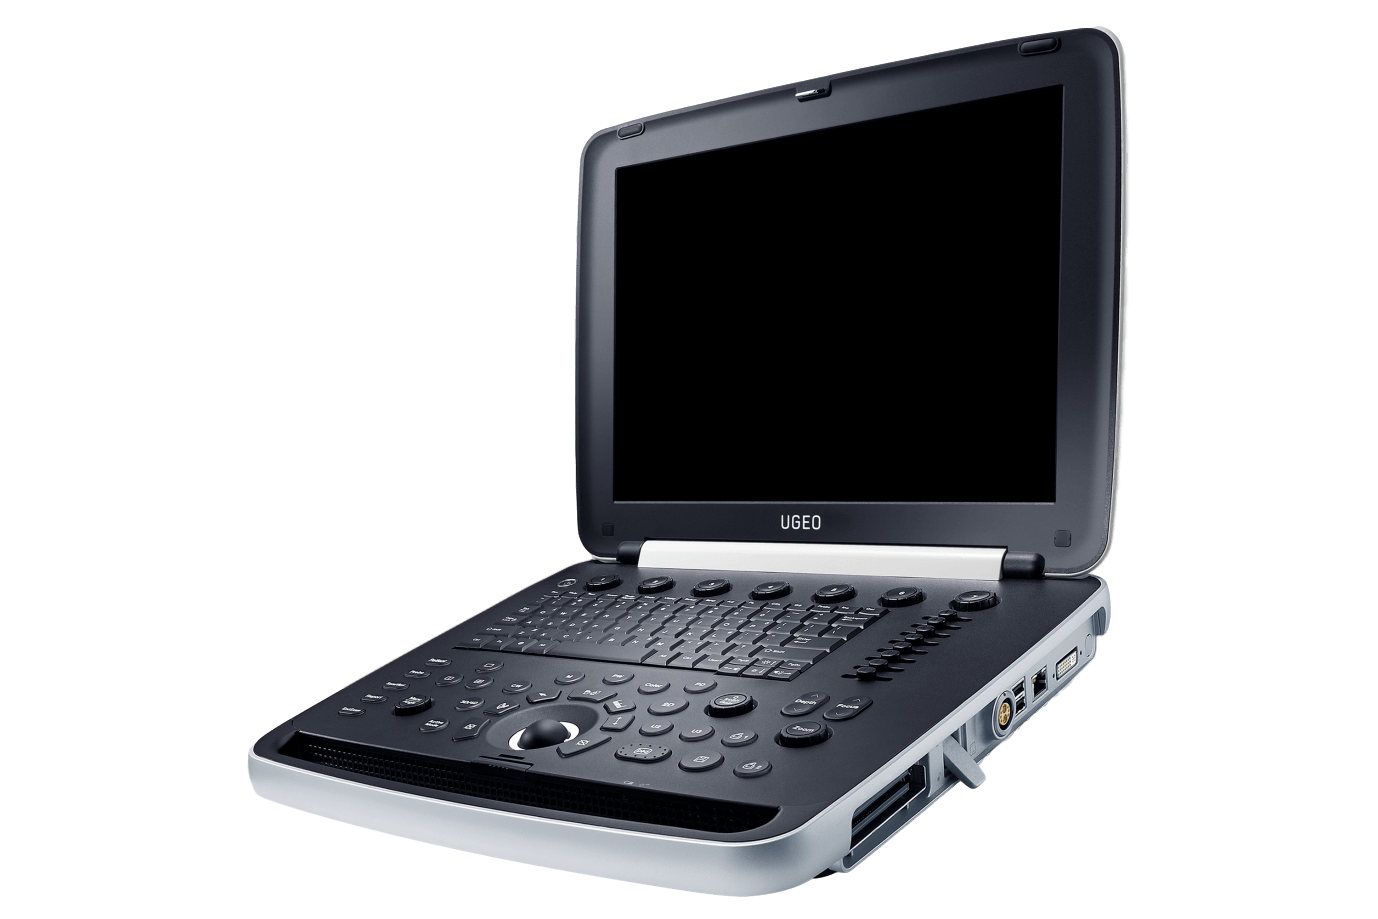

Оборудование для ультразвуковой диагностики Medison UGEO HM70A

Переносной ультразвуковой сканер является высокоточным диагностическим устройством. Он обеспечивает визуализацию на уровне стационарных экспертных систем. Аппарат работает с высокоплотными монокристальными датчиками.